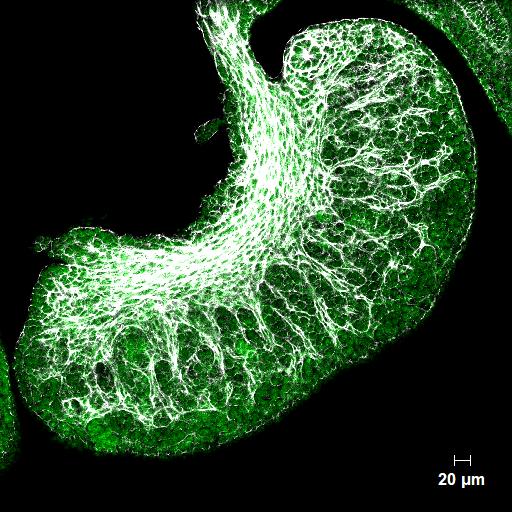

Developing mouse ovary showing the ingrowth of blood vessels (white) the cells of which will nourish the follicles that develop with each menstrual cycle in the adult.

Striations show segments of the ovary where the very first follicles are forming, most of which will have degenerated by the time a woman reaches adulthood.